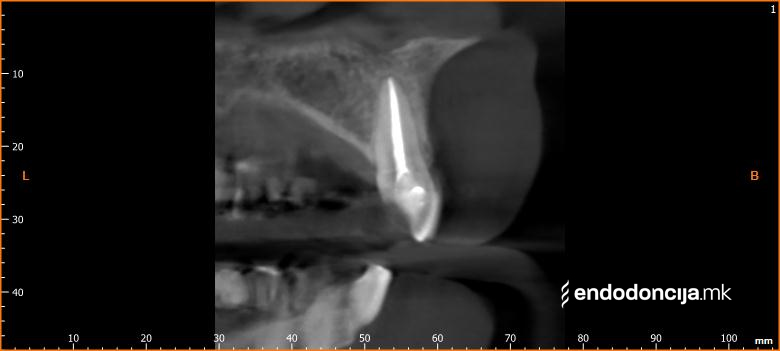

На специјализираниот оддел за ендодонција, нашите пациенти ги лекуваме на највисоко професионално и дијагностичко ниво. Опремени сме со најсовремени хируршки микроскопи, кои поддржуваат детален приказ и подготовка на коренот и нудат комплетно ново ниво на прецизност. Најновата ендодонтска опрема, инструментите и материјалите за полнење се во секојдневна употреба. На овој начин третманот станува пократок, дури и во комплицирани случаи, и се избегнува губење на забите.

Она што е импресивно е прецизноста на микроскопските третмани. Дури и кога каналите се потешко достапни, може да се лоцираат и исчистат така што релапсите се со помала веројатност. Спротивно на тоа, скриените канали често остануваат неоткриени во конвенционалниот третман на коренскиот канал и затоа не можат да се чистат. Бактериите можат да се размножуваат таму без пречки и да предизвикаат воспаленија. Ова често останува незабележано со години додека не се појави забоболка, а со тоа и компликации.

Зошто третман на коренскиот канал под микроскоп?